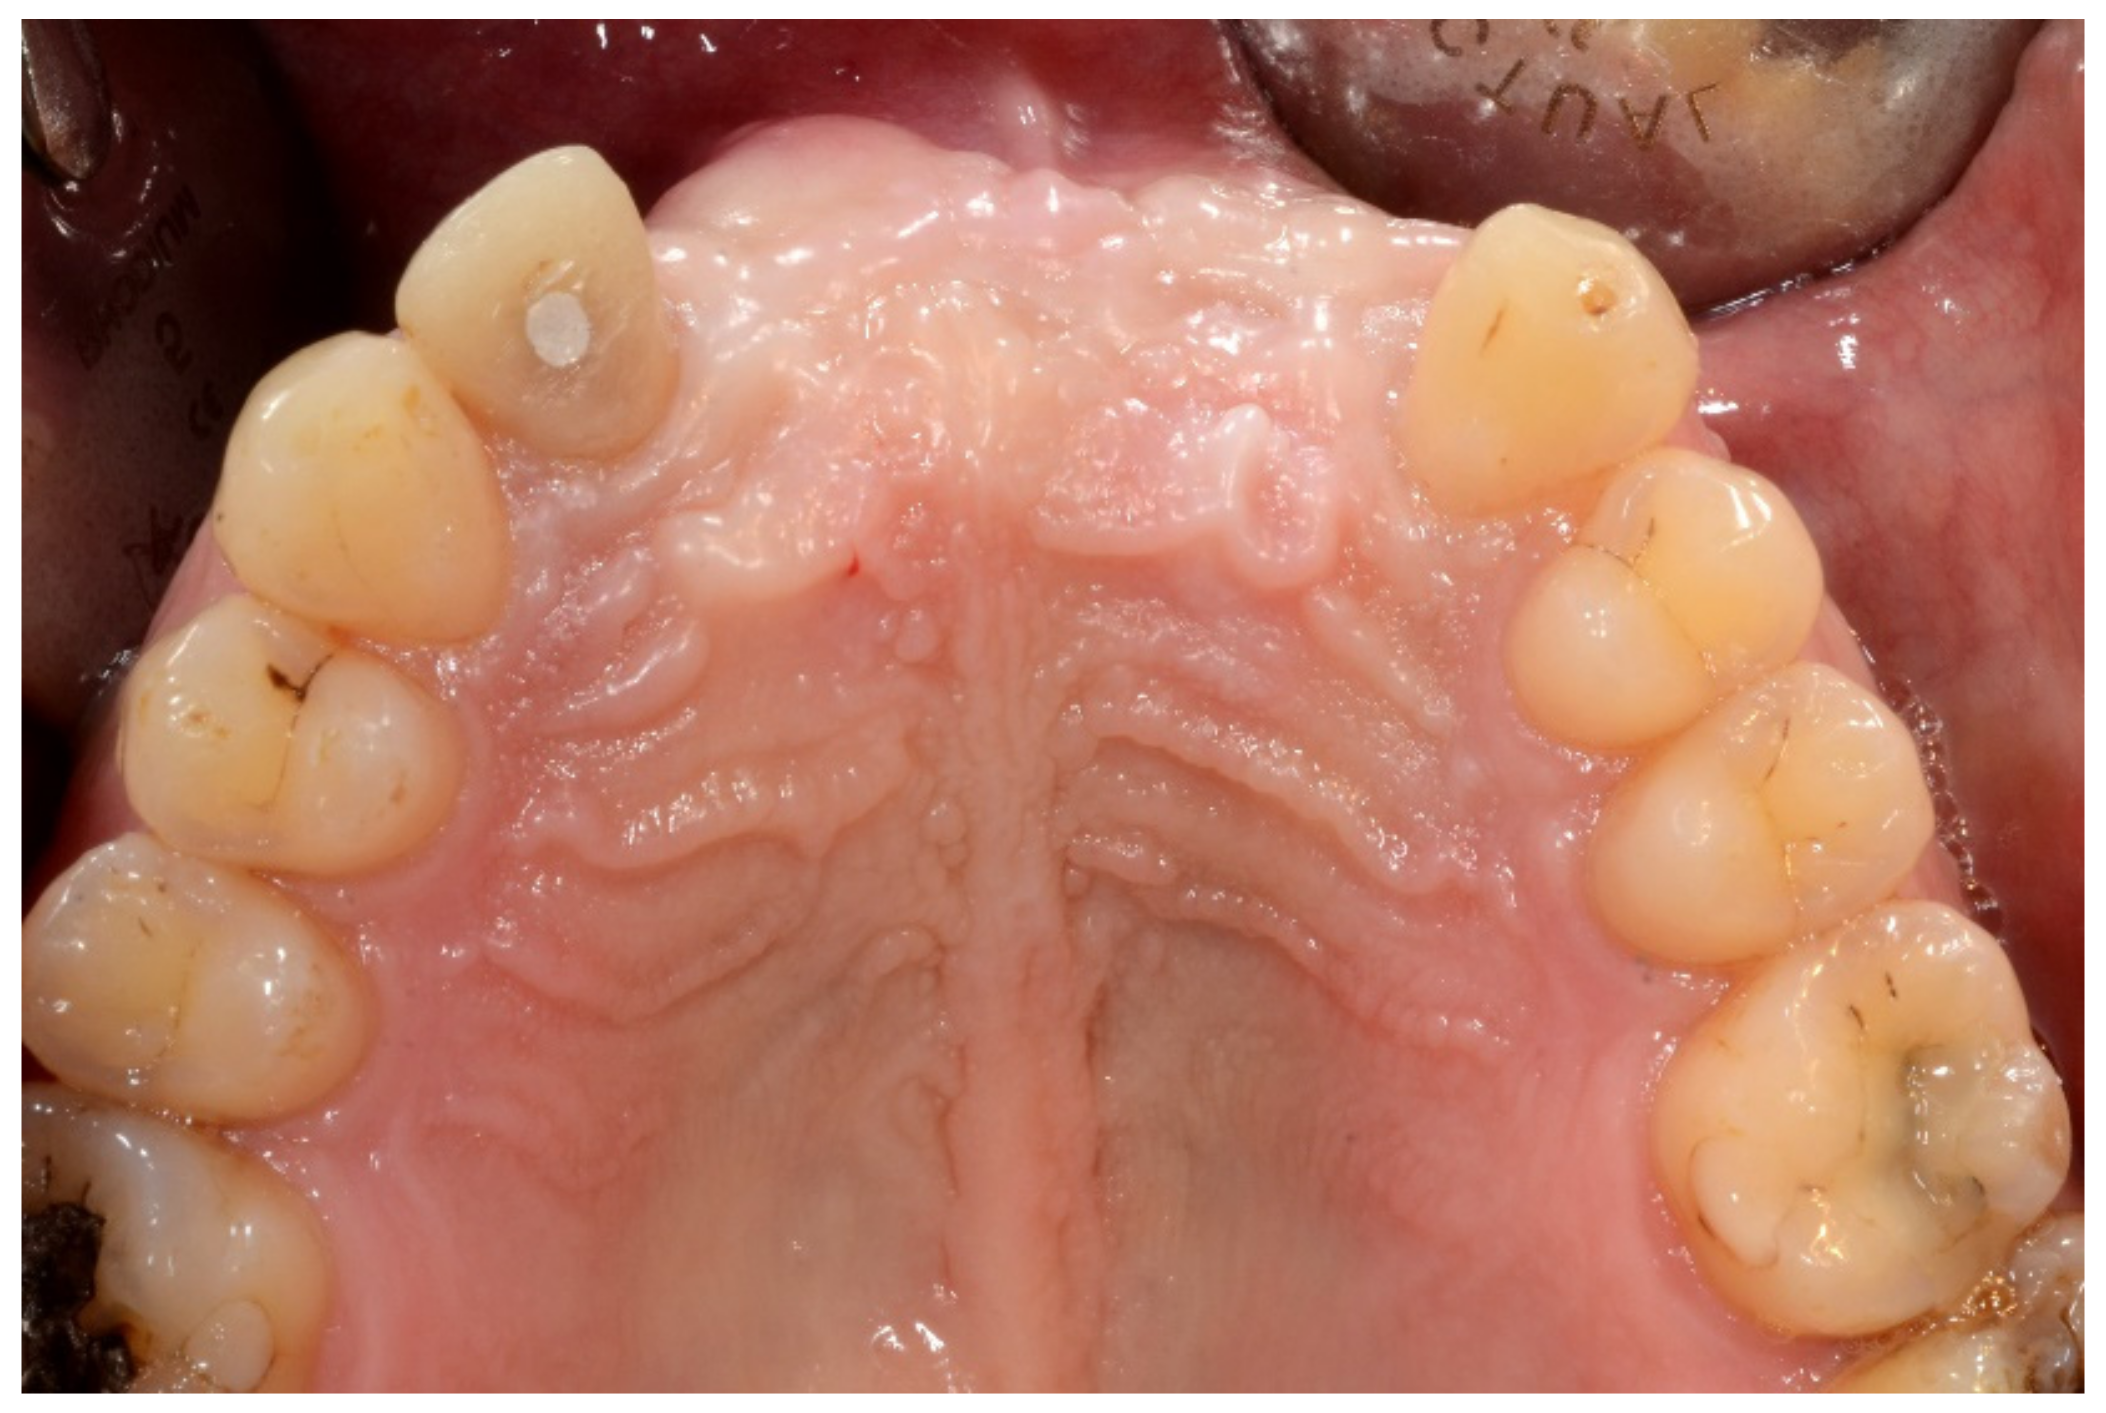

6.2.1. Severe Partial Edentulous Maxilla and Complete Edentulous Mandible (Maxillary and Mandibular Screw-Retained Implant-Supported Bridges)

6.2.2. Preoperative Documentation